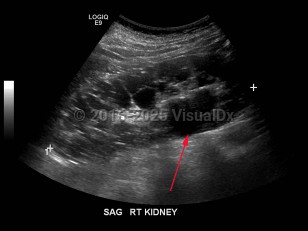

Polycystic kidney disease

Polycystic kidney disease (PKD) is an autosomal dominant (or, less often, autosomal recessive) disorder characterized by numerous cysts in the kidneys, which may lead to end-stage renal failure. The autosomal dominant trait is associated with mutations in either PKD1 (which encodes polycystin-1) or PKD2 (which encodes polycystin-2). A minority of patients with PKD have a defect unrelated to PKD1 or PKD2. PKD1 mutations are more common and correlate with an earlier age of disease onset as well as more rapid decline in renal function.

Patients with autosomal dominant inheritance usually manifest symptoms at around 30 years of age; symptoms include abdominal pain, hematuria, and high blood pressure. Hypertension is very common and precedes the onset of overt renal dysfunction. Complications specific to renal cysts include cyst rupture, cyst infection, and nephrolithiasis.

Patients may develop brain aneurysms and liver cysts. Typically, this has a strong familial pattern, and the risk of cerebral aneurysm in patients with PKD is highest in those who have family members who have had aneurysms.

Children with autosomal recessive inheritance often manifest in the first decade of life and may develop progressive renal failure and hepatic fibrosis. The autosomal recessive trait is associated with mutations to the PKHD1 gene.